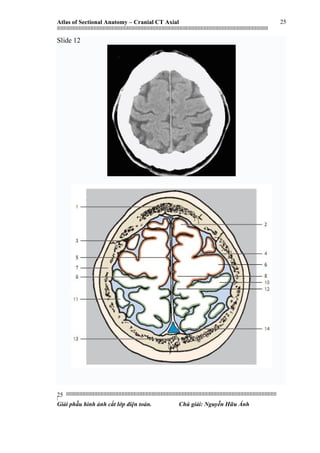

Slide 12

1. Frontal bone

2. Superior frontal gyrus

3. Coronal suture

4. Precentral sulcus

5. Falx cerebri

6. Precentral gyrus

7. Parietal bone

8. Paracentral lobule

9. Central sulcus

10. Postcentral gyrus

11. Superior parietal lobule

12. Precuneus

13. Sagittal suture

14. Superior sagittal sinus

1. Xoang trán

2. Hồi trán trên

3. Khớp vành

4. Rãnh trước trung tâm

5. Liềm não

6. Hồi trước trung tâm

7. Xương đỉnh

8. Thuỳ cạnh trung tâm

9. Rãnh trung tâm

10. Hồi sau trung tâm

11. Thuỳ đỉnh trên

12. Hồi trước chêm

13. Khớp dọc

14. Xoang tĩnh mạch dọc trên